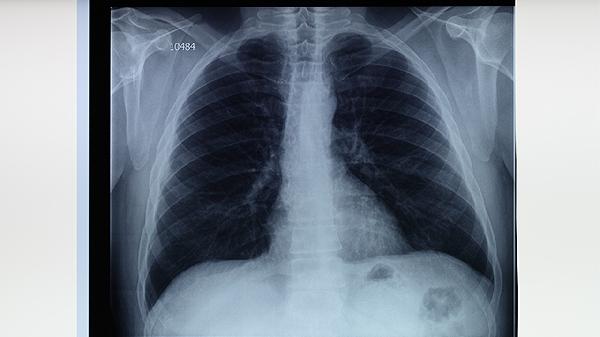

高危人群應每年進行胸部X線檢查,結(jié)核菌素試驗陽性者需做進一步評估。出現(xiàn)咳嗽咳痰超過2周、低熱盜汗等癥狀時,要及時做痰涂片和GeneXpert檢測。密切接觸者需接受預防性服藥,異煙肼通常需要連續(xù)服用6-9個月。